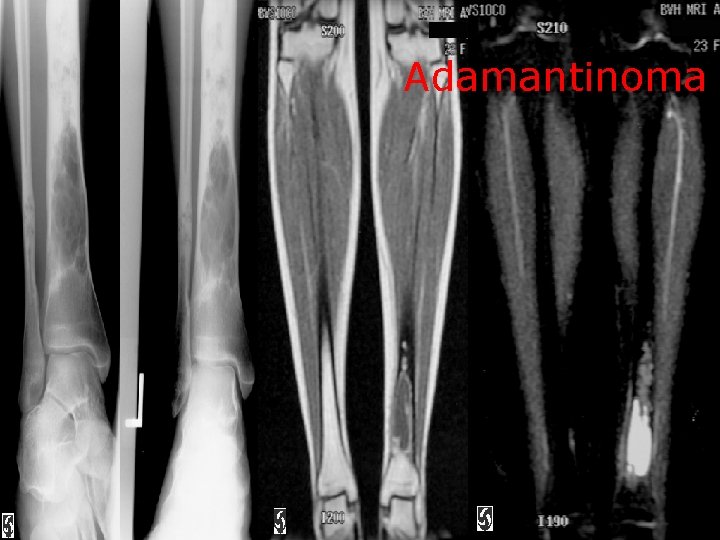

Adamantinoma

Concerning Malignant bone lesion: a. Chordoma os most common in the thoracolumbar spine b. (X ) 90% in basisphenoid and sacrum Fibrosarcoma is the commonest tumour 2 ry to paget’s disease c. (√ ) Adamantinoma occursin the tibia in over 90% of cases (√ ) d. Angiosarcoma has a soap bubble appearance at radiography e. (√) Chondroblastoma are typically found in the diaphysis (X ) they are epiphyseal lesions